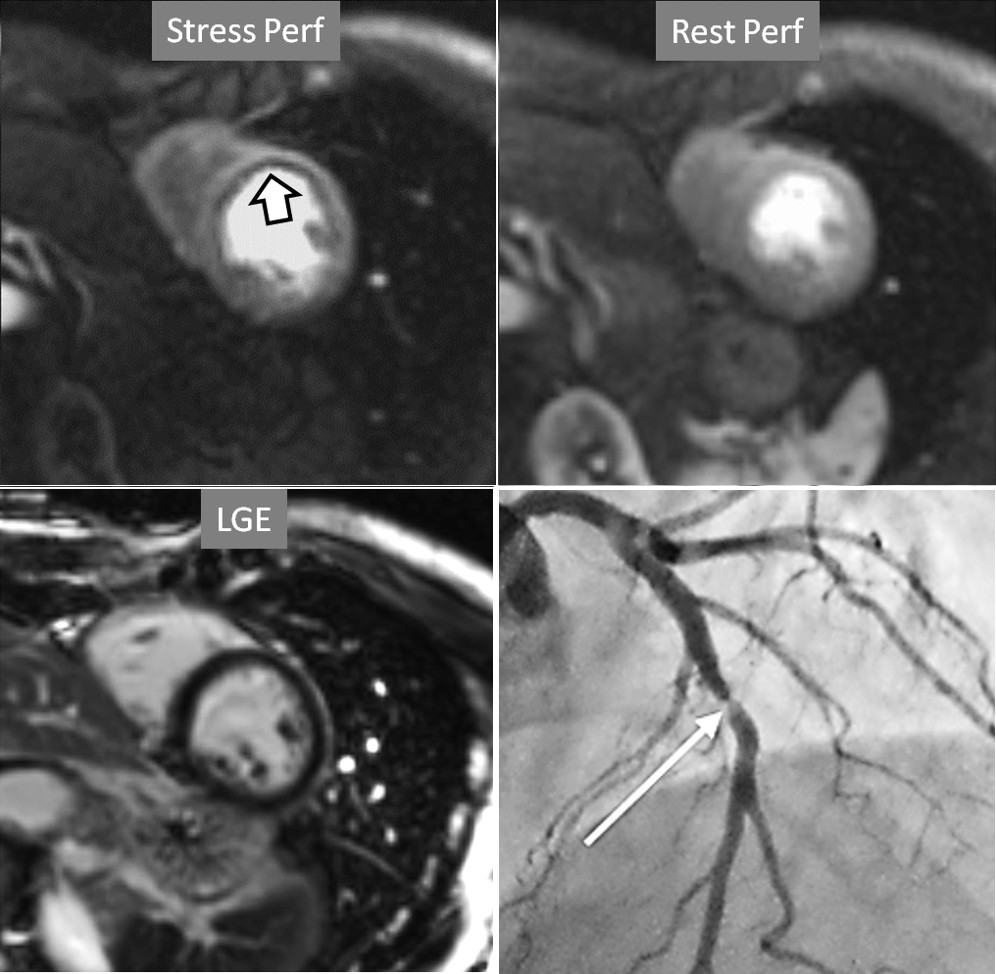

The most immediate and commonest method of analysis is the visual detection of a distinctive deficient increase in signal intensity of a region of the left ventricular myocardium during the first passage of a CA bolus under vasodilatory conditions lasting for at least 3 consecutive frames of the sequence. This perfusion defect should not be present at rest and should not correspond to an area of previous MI. The detection of such a defect is assumed to be due to a reduction in CFR of this territory which, when attributed to a particular coronary artery [39], allows for the conclusion of the presence of a significant epicardial stenosis in the vessel (Fig. 6).

Fig. 6.Single-vessel perfusion defect. Extensive subendocardial perfusion defect at the antero-septal region (arrow, on the upper left panel) not present at rest, in a region without LGE (lower left panel). Angiography proves this defect to be due to a tight stenosis of the LAD coronary artery (arrow, on the lower right panel).